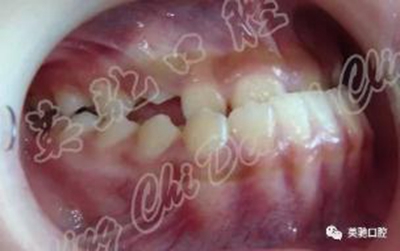

女性,就診時14歲。主訴:雙側(cè)耳屏前彈響3年。診斷:AngleⅢ類前牙反牙合。上頜發(fā)育不足,下頜前突,下前牙代償性舌傾明顯,右側(cè)上頜尖牙尚未完全萌出。雙側(cè)顳頜關(guān)節(jié)彈響,耳鳴。

治療:戴用小型下頜雙側(cè)調(diào)位牙合板后退下頜,同時粘固直絲托槽排齊整平上下牙列(除右上尖牙外)。在戴用后退位牙合板一月后,雙側(cè)關(guān)節(jié)彈響及耳鳴消失,繼續(xù)戴用共7個月。